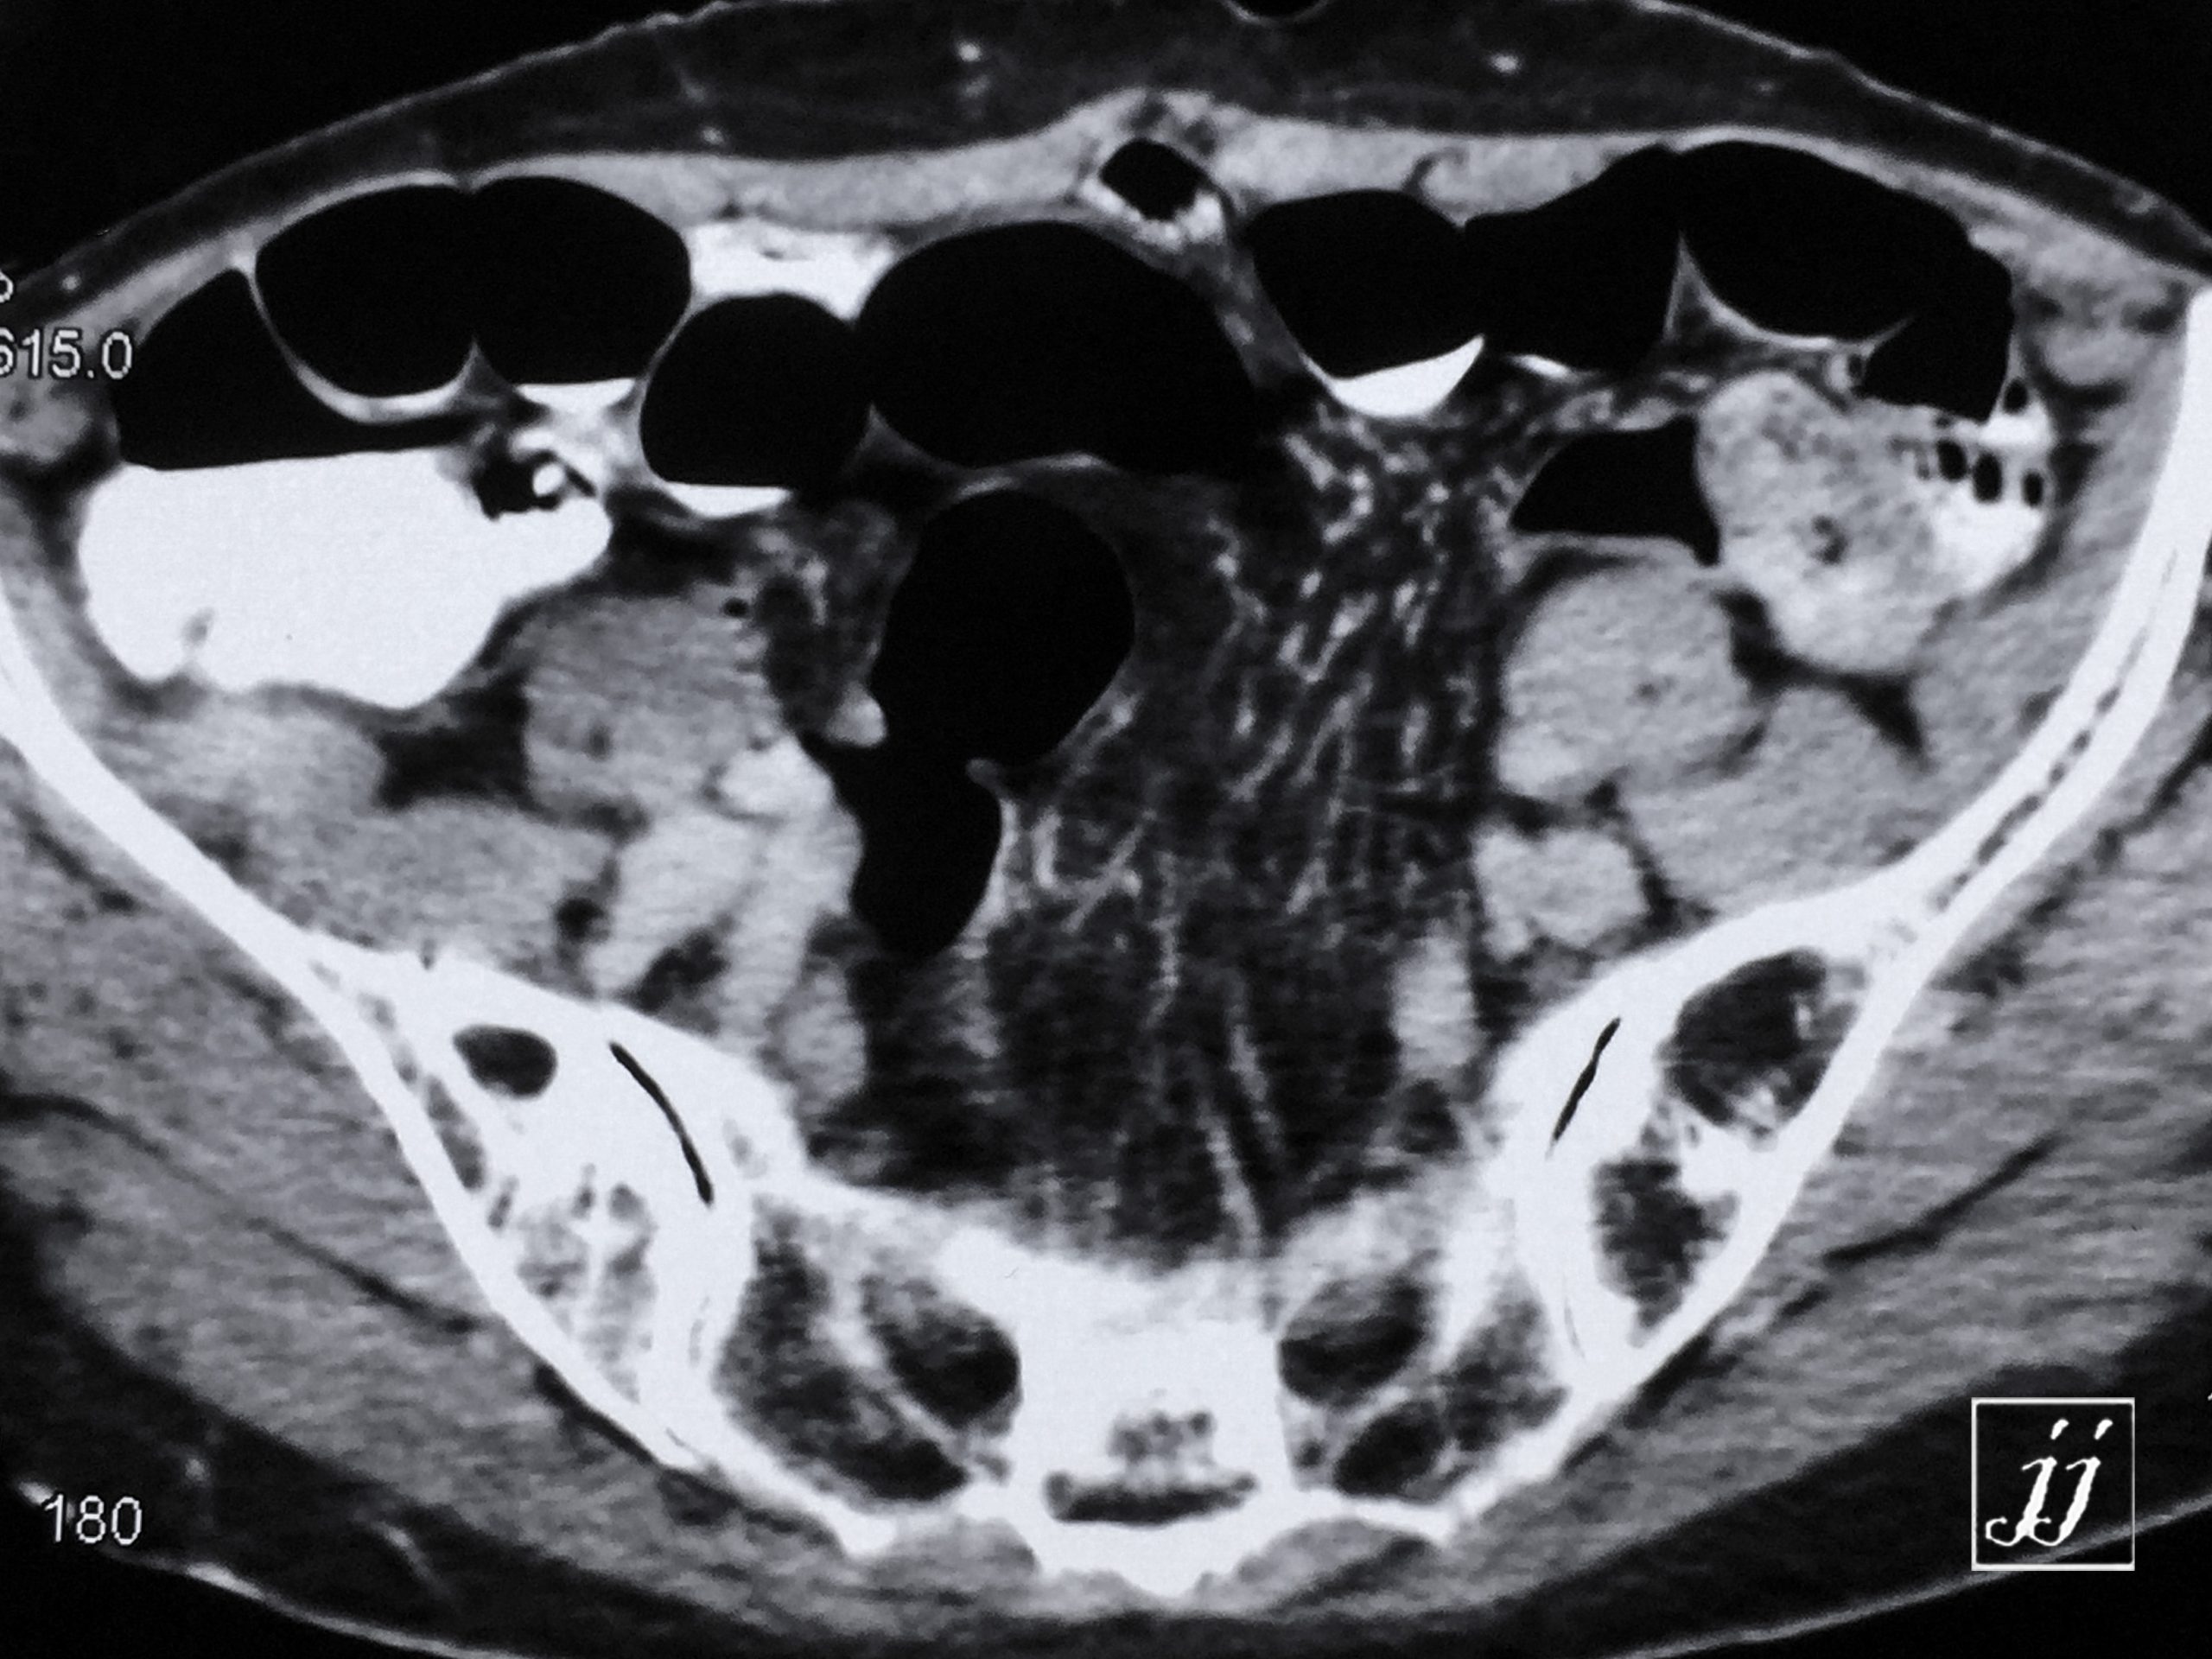

Abdomen- left kidney parapelvic cyst, and midline hernia (12)